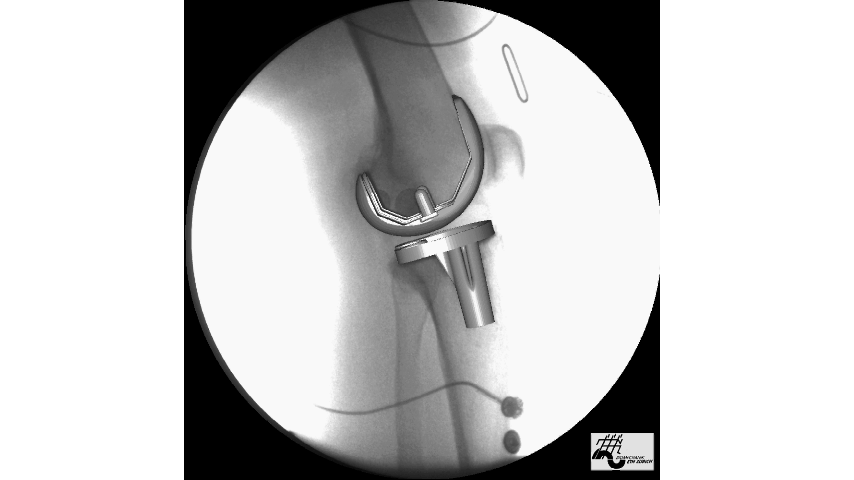

大家看下面这个动图,可能会觉得这个手术非常的简单,但这是模拟的动图,实际的手术操作非常复杂,要在膝关节的前方切一个纵行的切口,逐层的切开皮肤、皮下脂肪、筋膜、肌肉,进入关节囊,这个创伤是比较大的。之后要将影响关节功能比较多的骨赘,也就是骨质增生切除掉,再使用专用的模具逐渐修整关节的表面,最后替换上假体,之后等待假体固定坚固以后,反复的清洗关节腔,再逐层的将切口缝上。

这样一个手术过程,手术非常熟练的专家,换假体的过程需要20~40分钟左右,而切开再缝合的过程可能要一个小时。